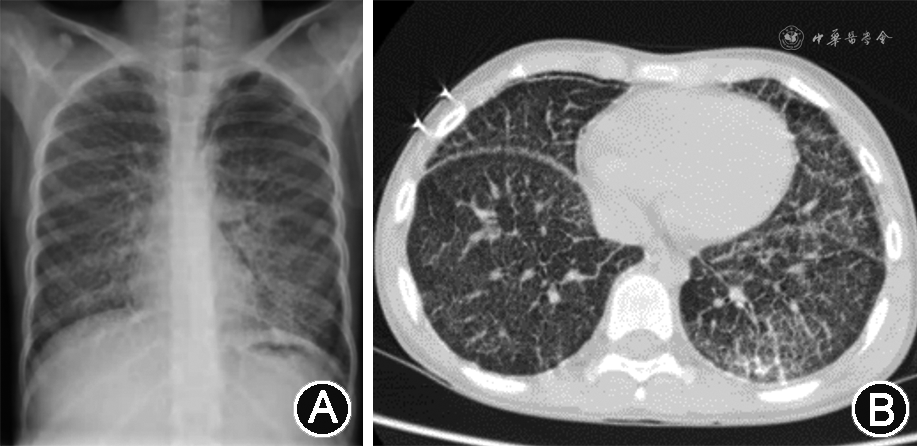

辅助检查:血常规,动脉血气分析,肝、肾功能均未见异常,结核分枝杆菌特异性细胞免疫反应检测、结核菌素试验、痰培养、痰涂片抗酸染色、肺泡灌洗液培养、肺泡灌洗液抗酸染色、血清结核抗体均为阴性,涎液化糖链抗原6 211 kU/L(参考值<500 kU/L),烟曲霉IgM抗体256.97 kAU/L(参考值 0~79.99 kAU/L)。胸X线片检查提示肺部间质性病变(图1A)。肺功能检查提示轻度阻塞性通气功能障碍,心脏超声未见异常,胸腹部增强磁共振成像见明显异常,胸部增强CT提示两肺弥漫间质病变,两侧胸膜钙化(图1B)。术后病理示肺泡腔内见多发破碎钙化结节,部分呈同心圆样改变,符合肺泡微石症表现(图2)。